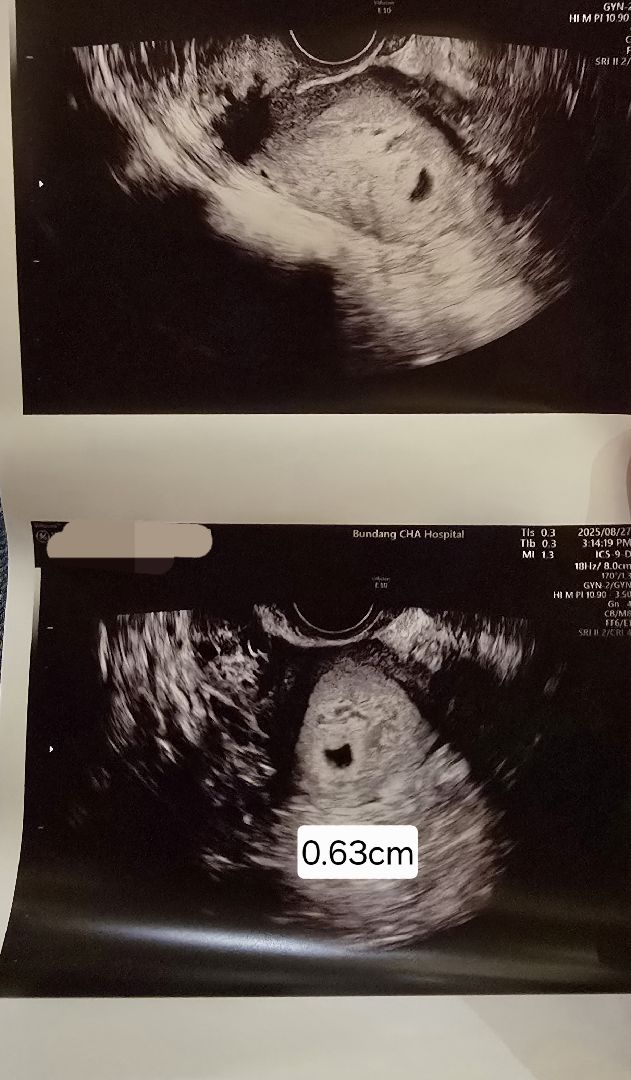

저도 오늘 5주차0일 인데 아기집만 봤어요

5주0일차 피검 9000이상인데 난황이 아직이네요

오늘 임테기 두 줄 이후 처음으로 병원가서 피검/초음파 봤습니다 아기집은 잘 보였고 선생님께서 아직 난황은 안보이고 아기집 사이즈는 괜찮다고 하셨는데 피검 수치는 병원 다녀온 이후 나온다고해서 몇시간 뒤 확인하니 9000이 넘더라구요 9000넘으면 난황 보인다던데 저는 아직 없는데.. 괜찮은걸까요..?ㅠㅠ 9000넘었는데 안보이신 분..계신가요 아니면 시기상 너무 이른건지 ㅠㅠ

저도 주수가 아직 난황 보일때가 아닌가봐요!!